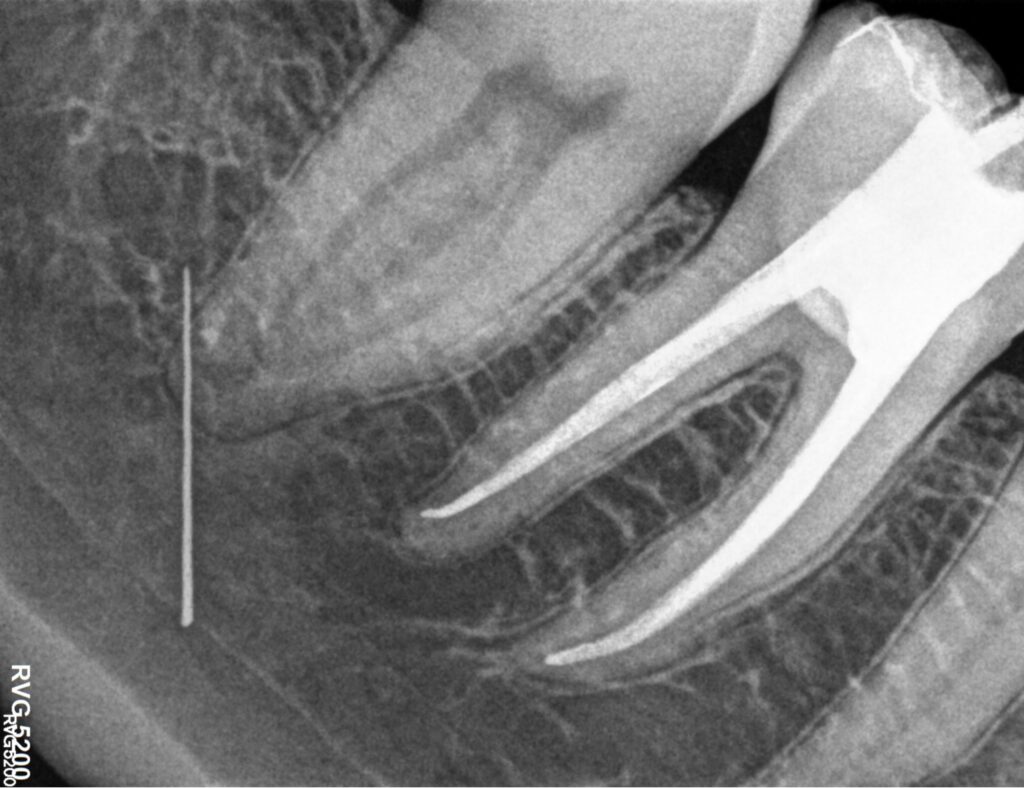

La Endodoncia es la rama de la odontología que se encarga del tratamiento de las patologías que afectan a los tejidos pulpares de los dientes como caries profundas, infecciones radiculares o fracturas.

Gracias a la endodoncia o tratamiento de conductos podemos conservar los dientes y su función. Cuando se deja que la caries dental evolucione o cuando el diente recibe un traumatismo importante éste termina afectando a los conductos donde está la pulpa dental (conocida como “nervio”). La acción de los microorganismos suele ser responsable de la infección e inflamación de la pulpa cuyo síntoma principal es el dolor agudo aunque a veces pueda pasar desapercibida. La evolución de esta inflamación termina en la “necrosis” o muerte de ésta, lo cual puede producir una infección o absceso a nivel óseo (flemón).

La Endodoncia limpia y conforma el interior de los conductos de las raíces dentales, sellándolos posteriormente impidiendo así la presencia de microorganismos en ellos. De este modo se consigue conservar el diente sin tener que extraerlo y la recuperación, en la mayoría de los casos, de la infección a nivel óseo.